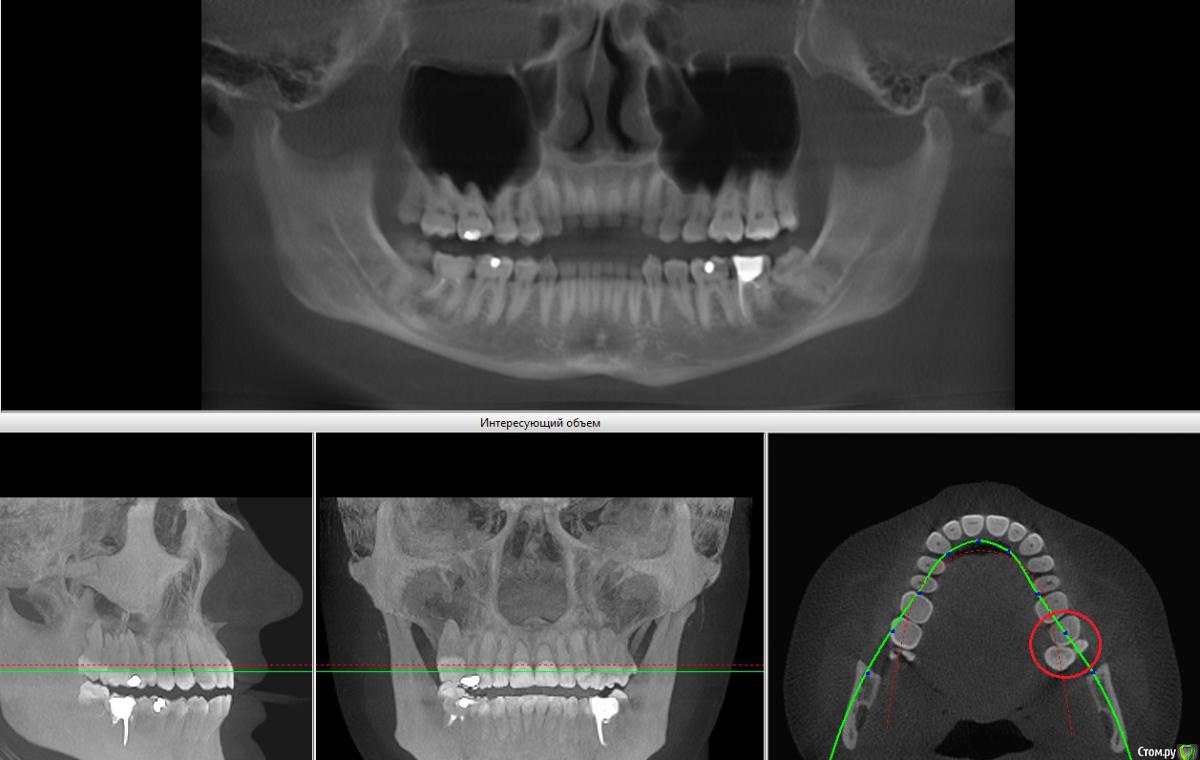

Вопрос 2. Если ставить брекеты. Только снизу или на обе челюсти? И как тогда быть с зубами мудрости наверху? С одной стороны у меня их девять :blink: (картинка 5, обведено красным кругом).

2. 1 или 2 челюсти решает врач. чаще всего две.  Зубов у Вас ровно столько , сколько должно быть  (в красном кружочке наложение верхней и нижней челюстей)